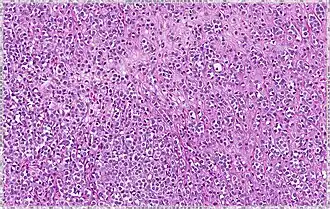

Classical | 40% | Round or ovoid cells with little cytoplasm in a single-file infiltrating pattern, sometimes concentrically giving a targetoid pattern | ![]() |